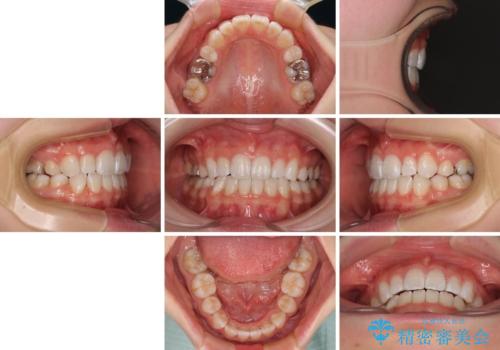

4本の歯を抜歯したことで、飛び出していた口元が引っ込み、横顔が大きく改善されました。